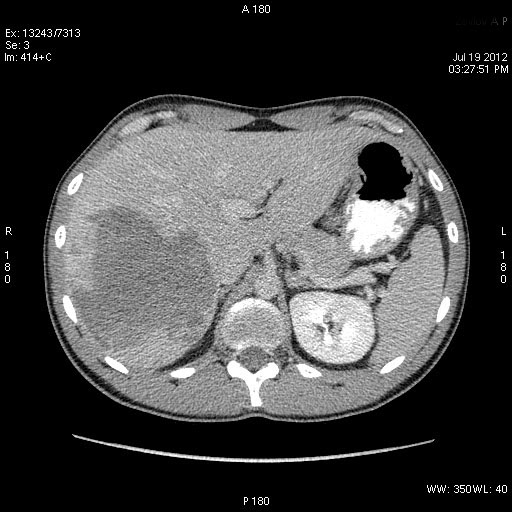

КТ через день

После КТ хирурги заказали дренирование "абсцесса".

Выполнена диагностическая пункция из 4х участков, получена только кровь.

Гигантская капилярная гемангиома печени.

Ангиографию надо назначить или УЗИ с контрастированием.